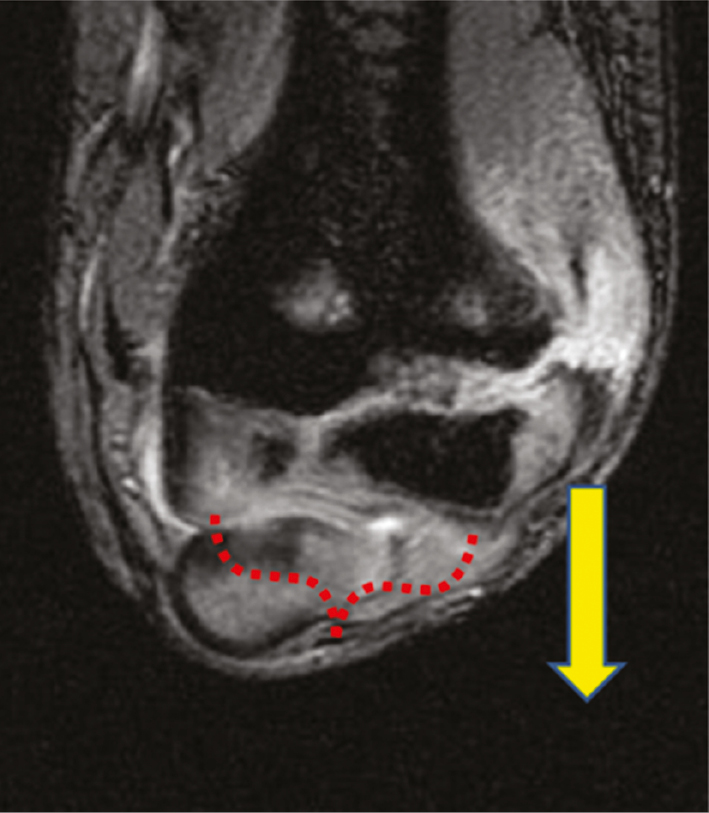

Most lateral condyle fractures result from a fall on the outstretched upper extremity and the varus force leads the extensor mechanism to pull the lateral condyle off to varying degrees. Minimally displaced fractures (2–4 mm) will hinge laterally and have an intact or minimally displaced articular surface that can prevent displacement and facilitate reduction with direct pressure (Figure 1).

Figure 1. The vast majority of lateral condyle fractures result from avulsion of the lateral condyle with the arm in varus. Minimally displaced fractures may have an intact or minimally displaced articular hinge that facilitates closed reduction (red bracket). While an archaic classification, this fracture represents a Milch 2 fracture.